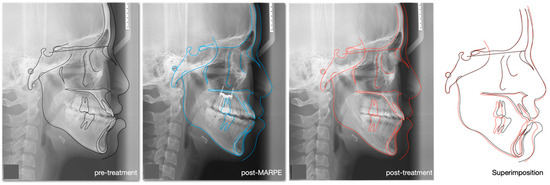

| SNA | 81° ± 3° | 81° | 81.5° | 81° |

| SNB | 78° ± 3° | 83.5° | 81.5° | 81.5° |

| ANB | 3° ± 2° | −2.5° | 0° | −0.5° |

| Maxillary inclination (S-N/ANS-PNS) | 8° ± 3° | 8° | 8° | 8° |

| MMPA | 27° ± 3° | 28° | 31° | 30° |

| LFH % | 55% ± 2% | 58.5% | 58.7% | 58.6% |

| Upper incisor to Max. plane | 108° ± 6° | 126.5° | 126.5° | 126° |

| Lower incisor to Mand. Plane | 93° ± 6° | 94° | 92° | 83° |

| Lower incisor to A-Po line | 1 ± 1 mm | +12.5 mm | +8 mm | +5 mm |

| Inter-incisal angle | 133° ± 10° | 111° | 110° | 120° |

| Upper lip-E line | −2 ± 2 mm | −3 mm | −2 mm | −3 mm |

| Lower lip-E line | 0 ± 2 mm | +4 mm | +3 mm | −1 mm |